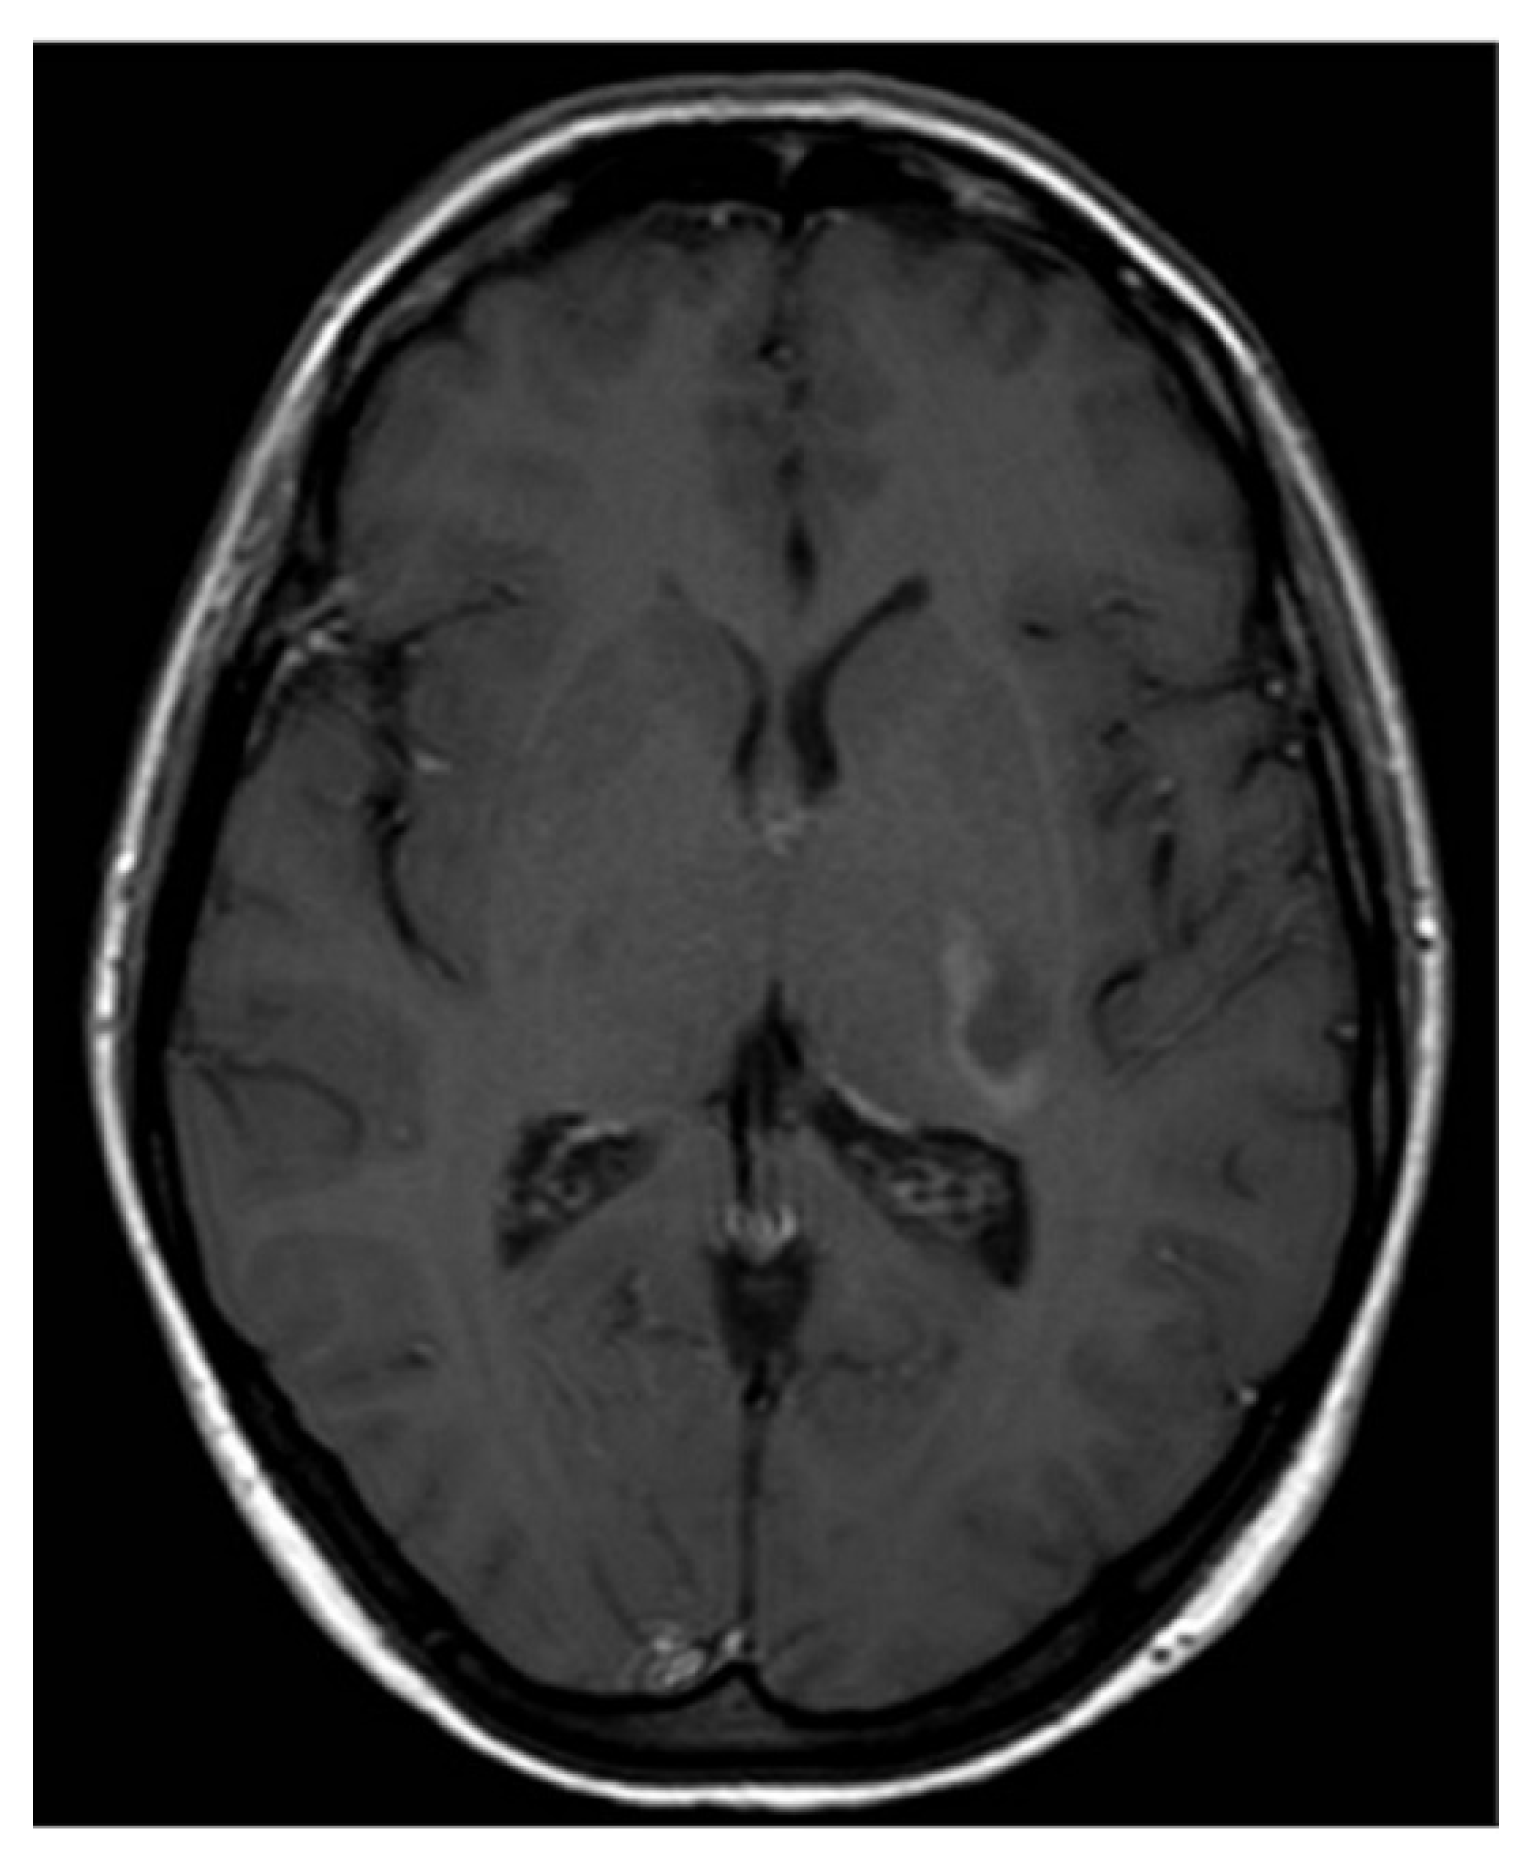

Subsequent magnetic resonance imaging (MRI) of the brain and C-spine revealed an area of hyperintense lesion on T2-weighted imaging involving the posterior limb of the internal capsule, adjacent to the left posterior thalamus with perilesional oedema (Figure 1 and Figure 2). Further hyperintensities were noted in the left frontotemporal region. These lesions demonstrated incomplete ring enhancement with gadolinium and facilitated diffusion restriction, consistent with acute demyelinating lesions. The lesions on the scan did not meet the MAGNIMS criteria for a multiple sclerosis diagnosis.

Figure 2.

T1-weighted axial MRI post gadolinium.